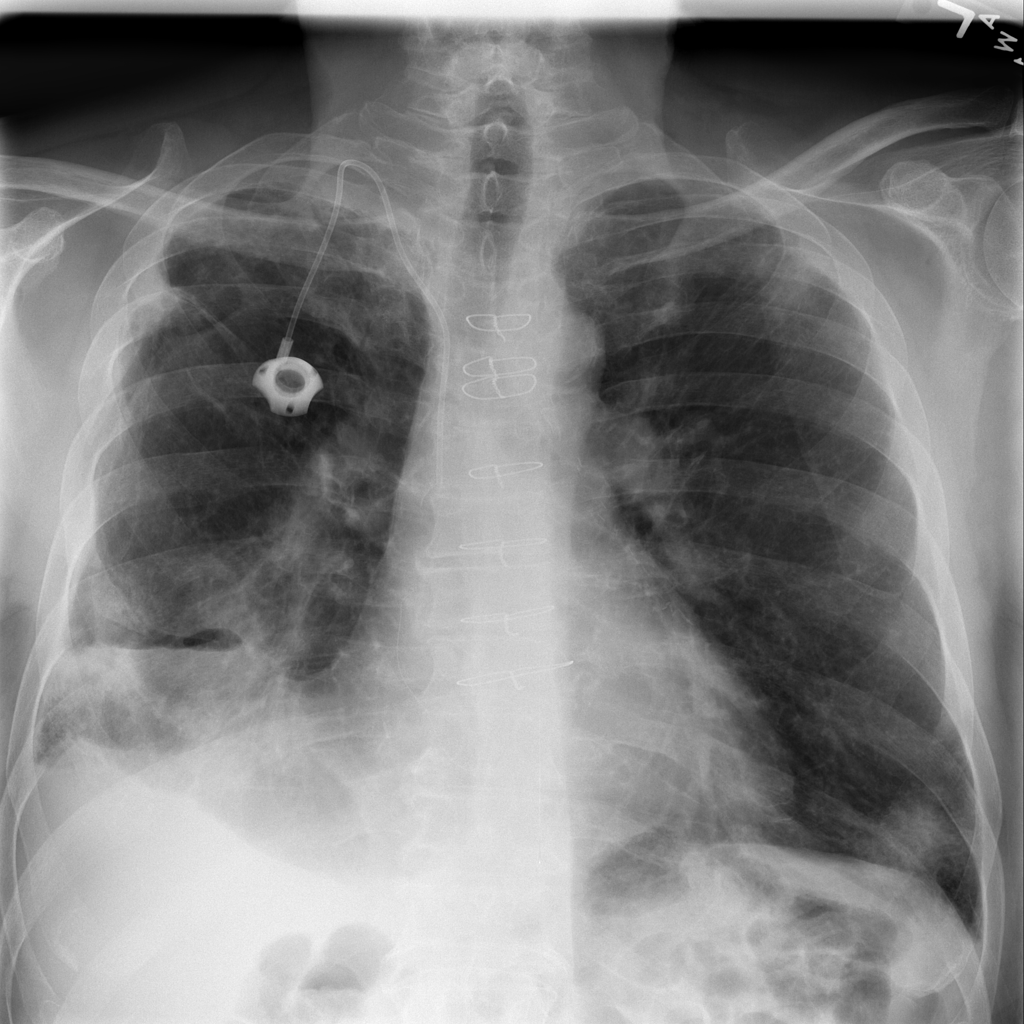

Mass

A mass is a larger focal opacity or lesion seen on the image. It is a descriptive finding that can have several causes and usually needs more imaging or clinical context to characterize.

PAT-C0E5 · IMG-001Mass

PAT-C0E5 · IMG-001

PA